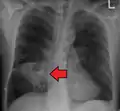

Pulmonary abscess on CXR